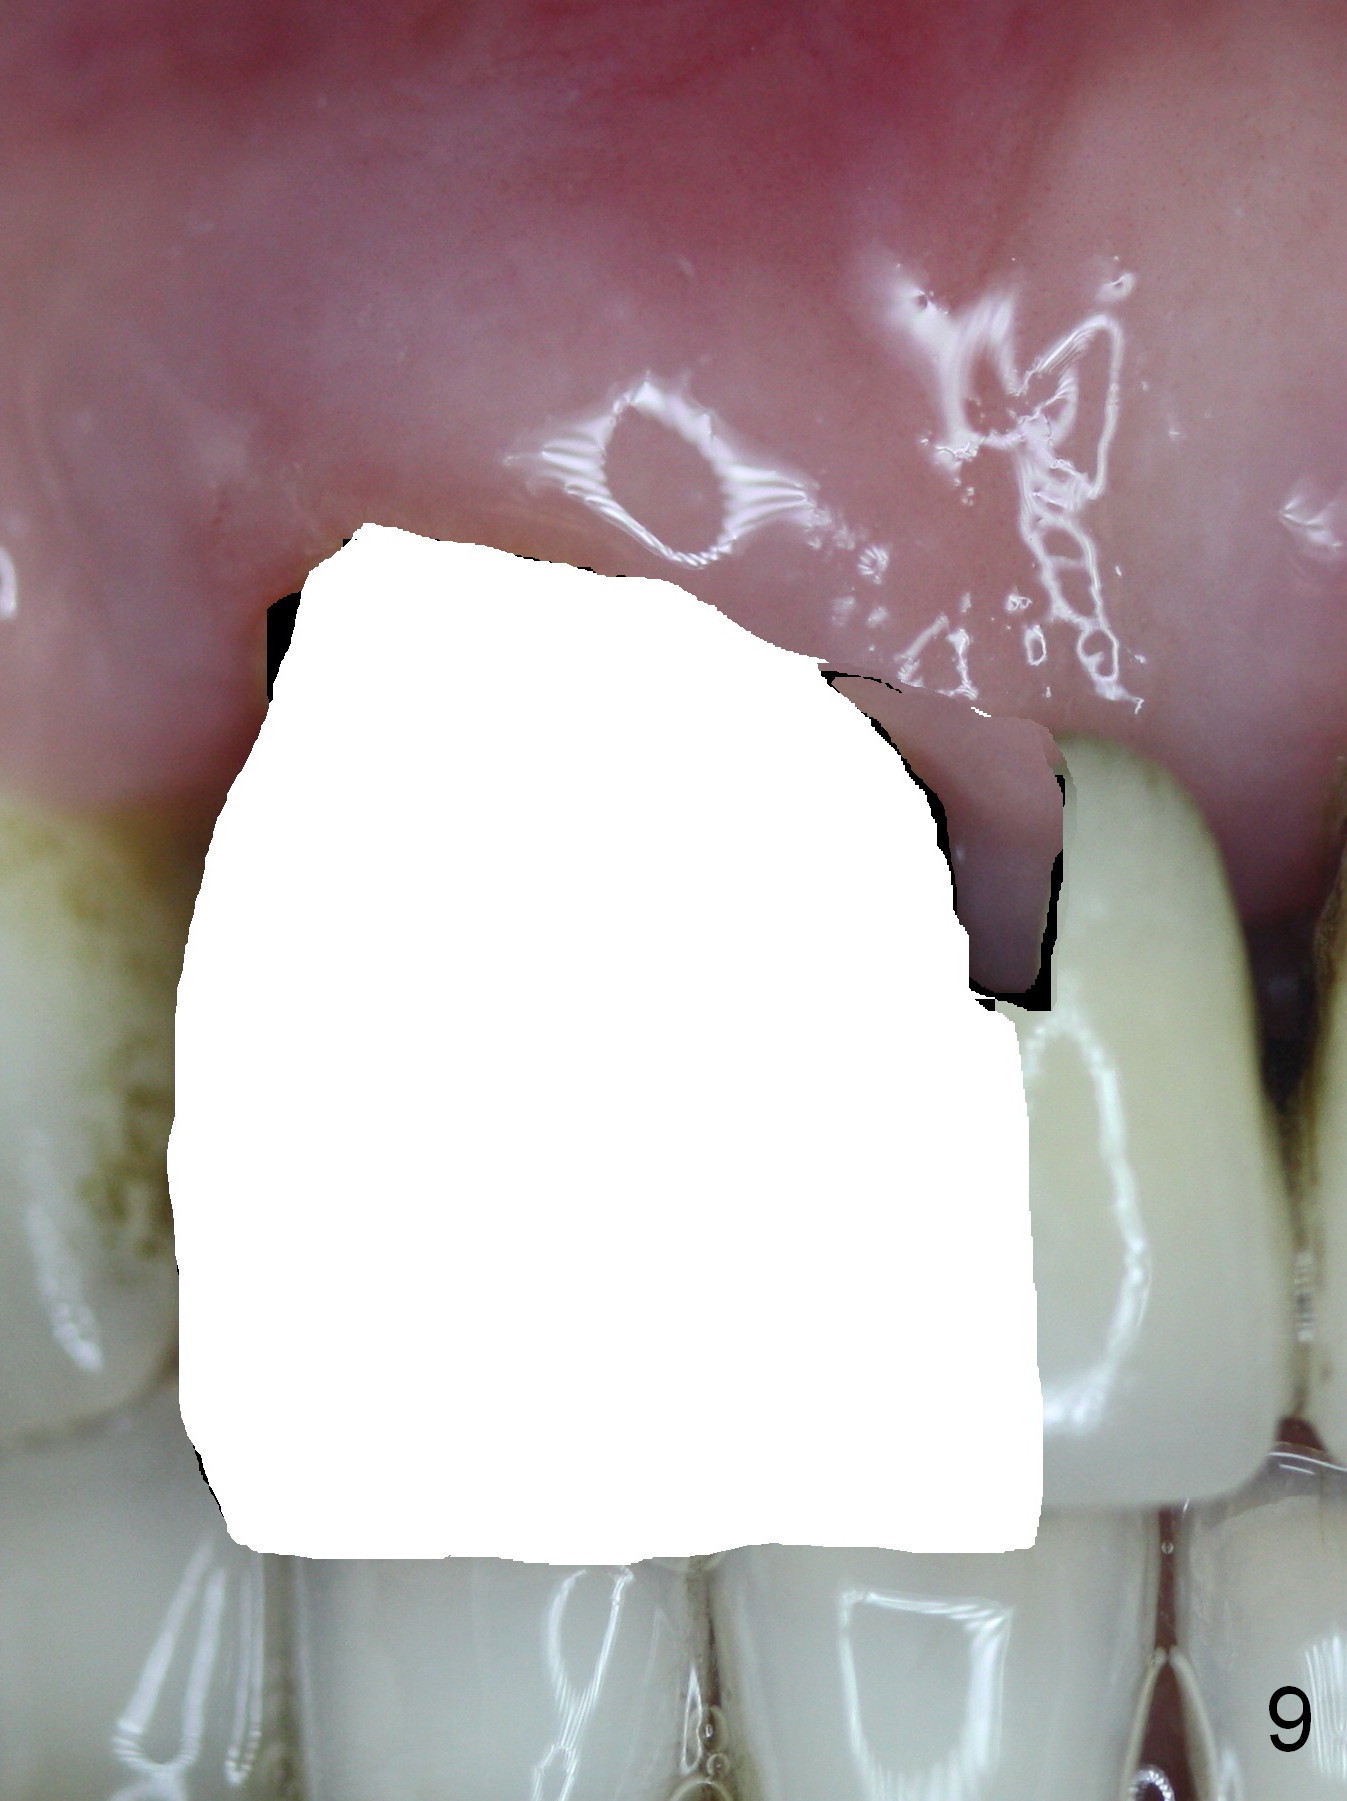

The 74-year-old patient is excited about having 3 implants placed without discomfort (1,2). He wants to take care of a loose FPD spanning from #8 to 9 (Fig.1). It appears that #8 is non-salvageable (Fig.2 * with deep pockets). There is severe bone loss around the affected tooth (Fig.3; Osteotape is expected for buccal and lingual defects). In addition, the Incisive Canal is abnormally large (arrowheads). The coronal end of a 4.5x20 mm implant and a 3.5x5 mm abutment will be slightly deviated mesially (Fig.4), since the 3-unit FPD will be converted to 2 single unit crowns. Surgical guide is ready. The 1st step is to section between #8 and the pontic (Fig.5; green outline: implant; red: abutment). If primary stability is low, the immediate provisional (Fig.8 white area) will be bonded the tooth #7 and the pontic as a supplementary measure (blue areas). Once the implant is osteointegrated, the distal portion of the pontic (Fig.7 *) will be removed. Acrylic is added to the mesial portion of the provisional (Fig.8 *) so that the papilla (P in Fig.7) will be pushed mesially and incisally (Fig.8 arrowheads). The step will be repeated a few weeks later (Fig.9). It could be done bilaterally at the same time by removing #9 crown and converting to the provisional. Finally the pontic will be removed. Two relatively wide crowns will be fabricated if the patient is satisfied with the provisional.